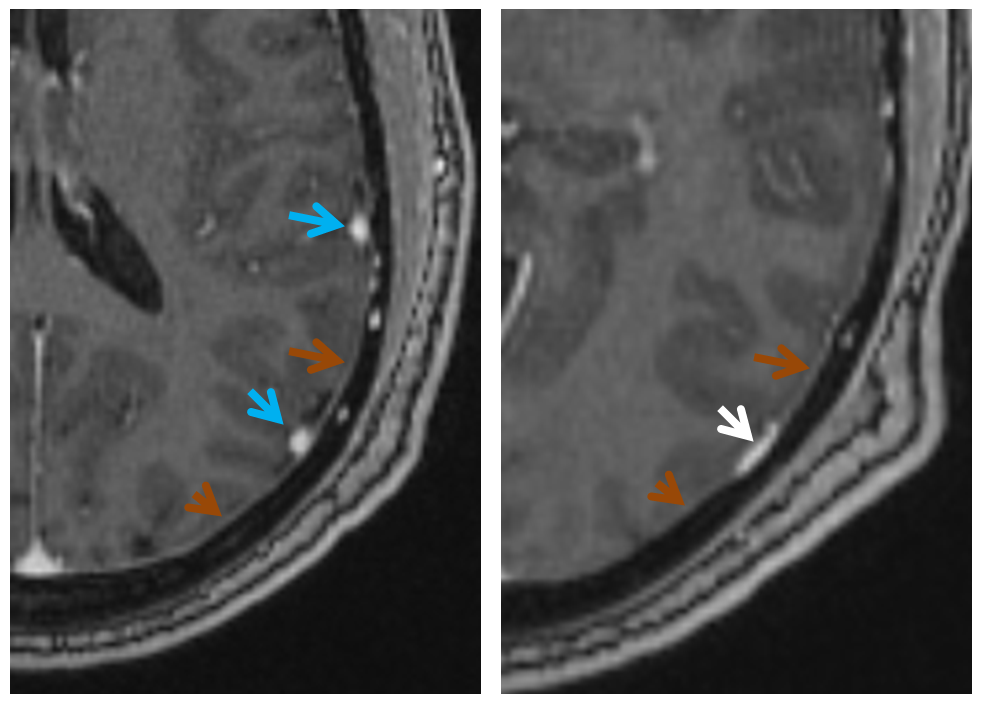

MRI of the same patient shows the characteristic rounded appearance of the cortical vein (light blue arrows), located just medial / deep to the dura (brown arrows), as distinct from the flattened, oval look of the dural sinus (white arrow). The post-contrast high-resolution T1-weighted images are the best way to look for dural sinuses like this one on non-invasive imaging